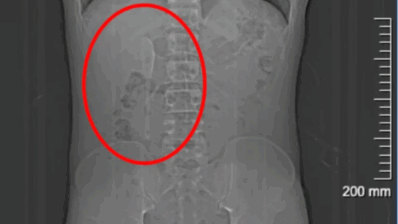

Cirurgia retira colher do intestino de homem que achava ter sonhado engolir objeto

30 jun

Ásia

Homem descobre que escova de dente engolida na infância estava presa no intestino há 52 anos

24 jun

Cientistas avaliam a hipótese de o item ter sido colocado como parte de um ritual funerário   Foto: Reprodução/Marzena Ożarek-Szilke/Universidade de Wrocław A múmia egípcia de um menino, que morreu por volta dos 8 anos, virou objeto de um estudo científico. A pesquisa já permitiu identificar sua idade e provável origem, mas a causa da…